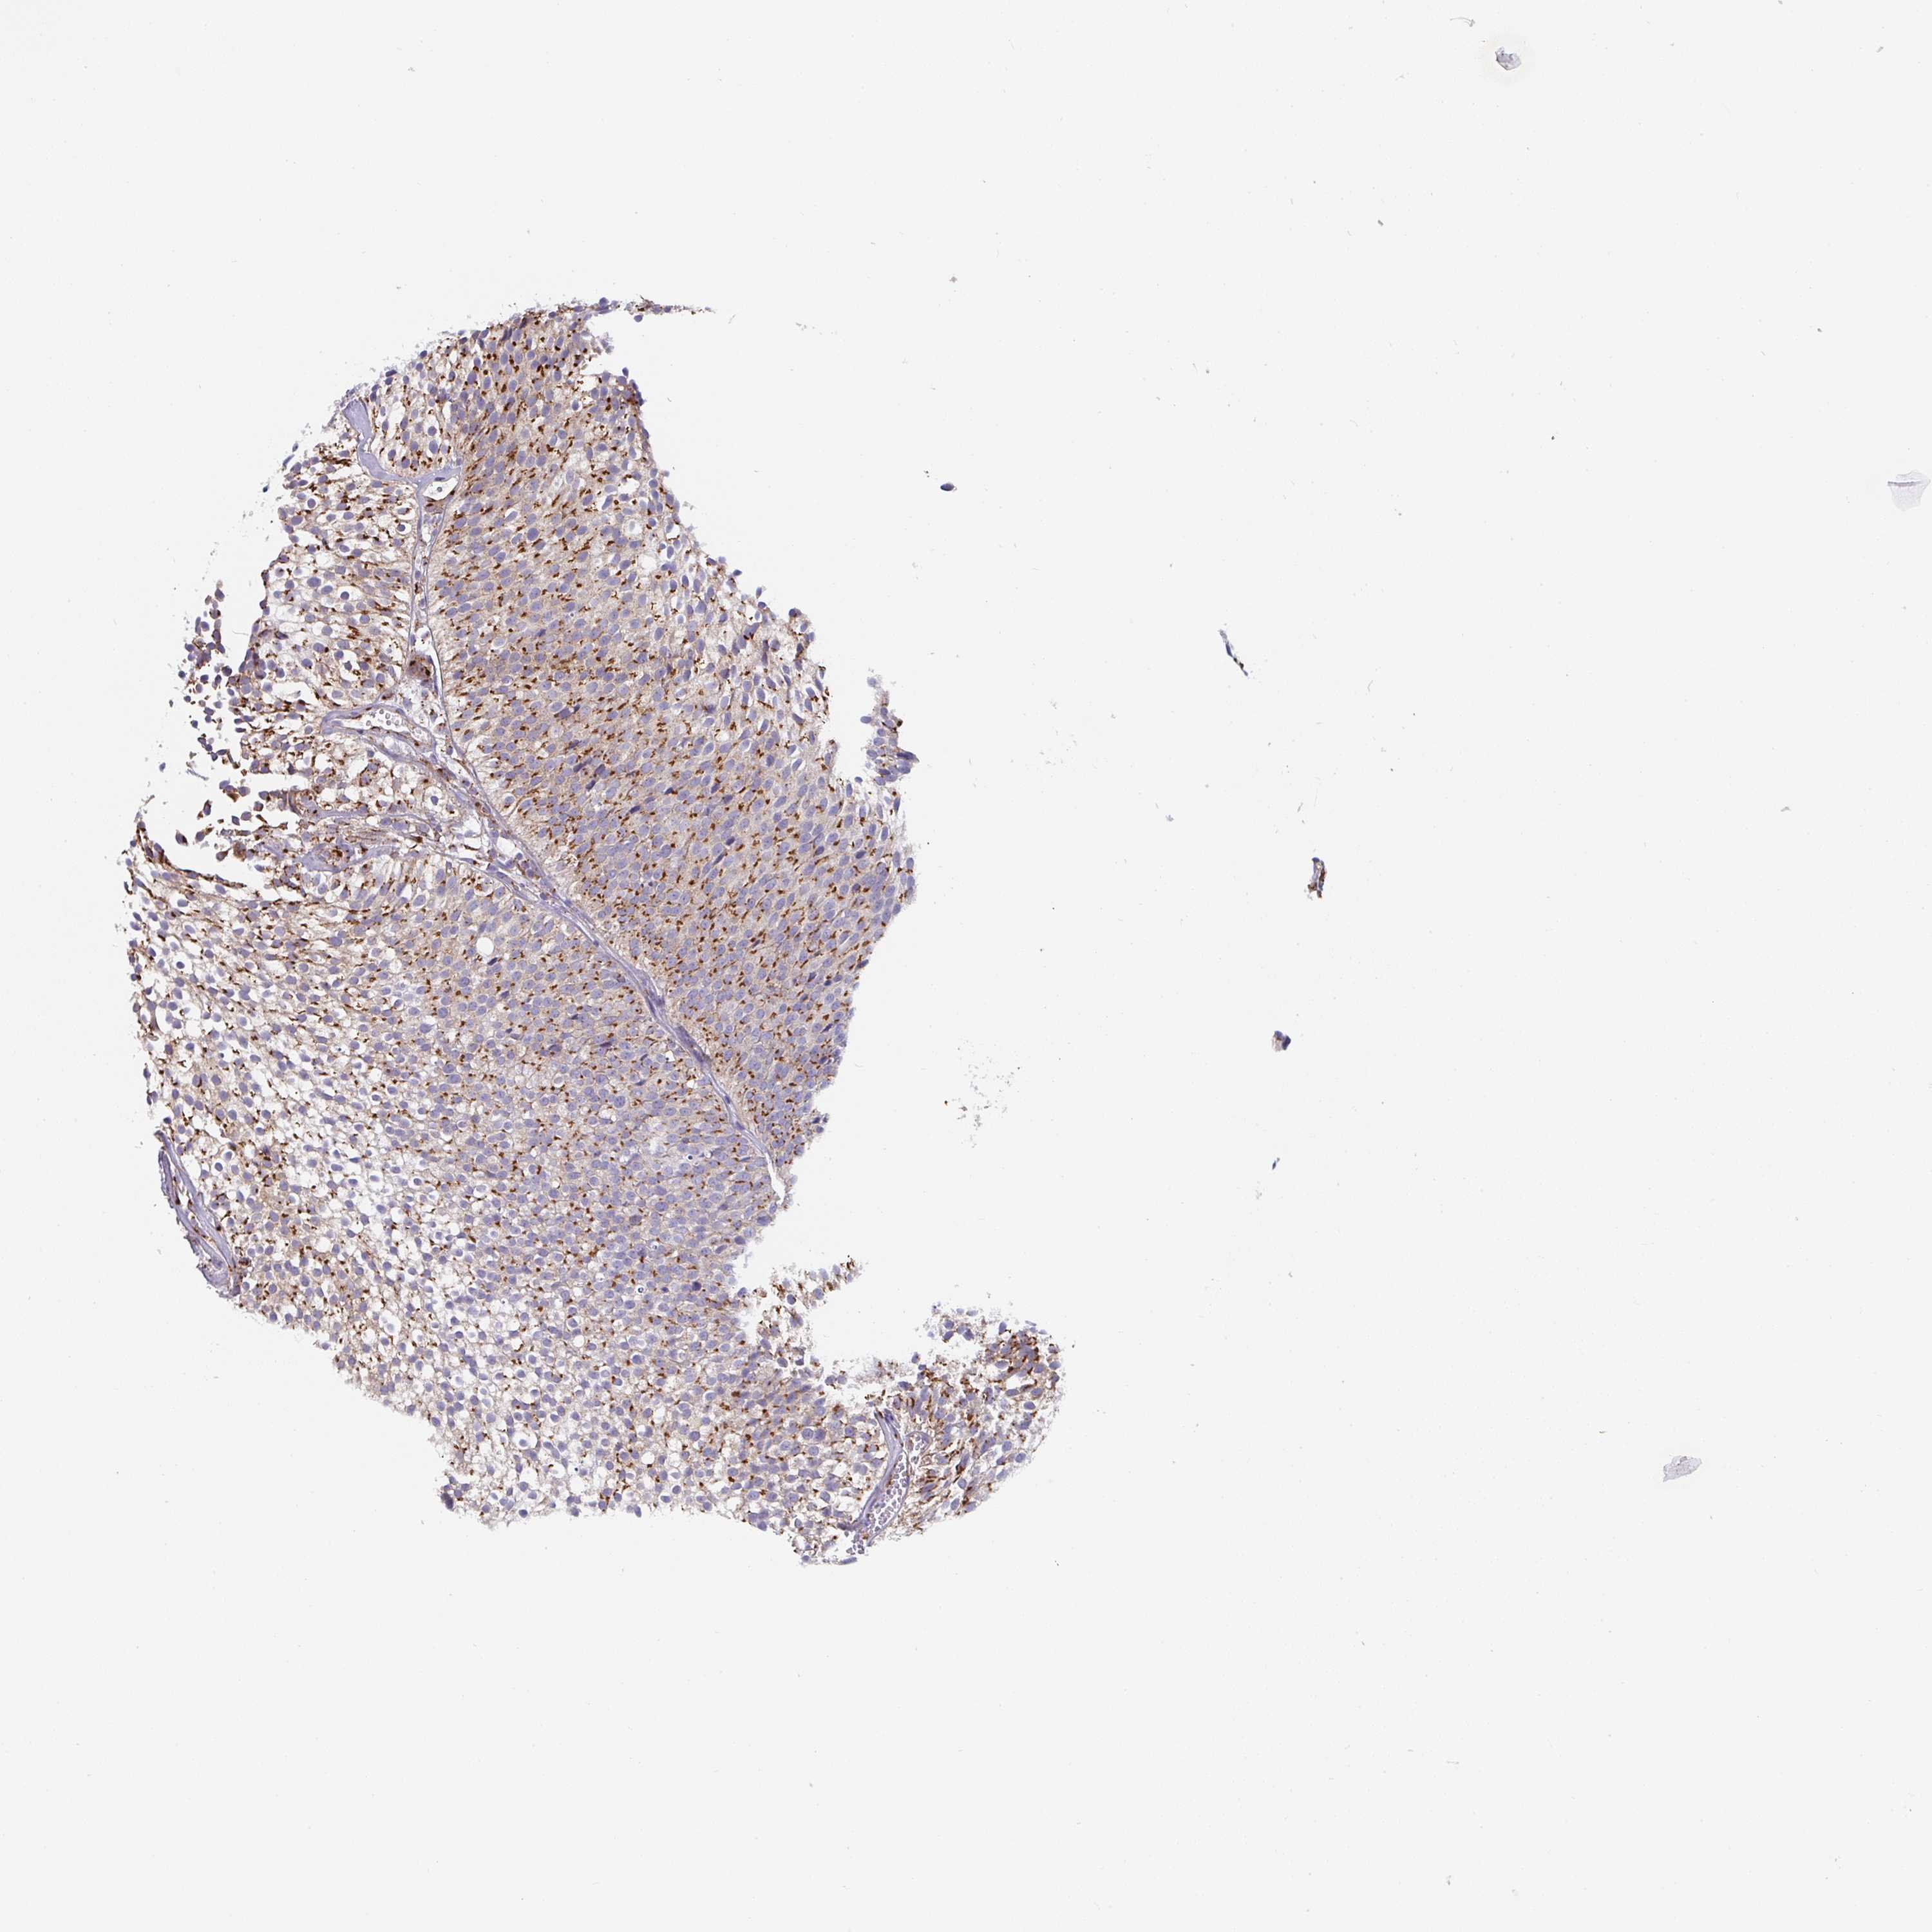

UROTHELIAL CANCER - Protein expressioni

A mouse-over function shows sample information and annotation data. Click on an image to view it in a full screen mode. Samples can be filtered based on level of antibody staining by selecting one or several of the following categories: high, medium, low and not detected. The assay and annotation is described here.

Antibody stainingi

Antibody staining in the annotated cell types in the current human tissue is reported as not detected, low, medium, or high, based on conventional immunohistochemistry profiling in selected tissues. This score is based on the combination of the staining intensity and fraction of stained cells.

Each image is clickable and will lead to virtual microscopy that enables deeper exploration of all samples and also displays staining intensity scores, fraction scores and subcellular localization as well as patient and tissue information for each sample.

Antibody HPA058492

Staining

High

Medium

Low

Not detected

Intensity

Strong

Moderate

Weak

Negative

Quantity

>75%

75%-25%

<25%

None

Location

Nuclear

Cytoplasmic/membranous

Cytoplasmic/membranous,nuclear

Urothelial carcinoma, High grade

Urothelial carcinoma, Low grade